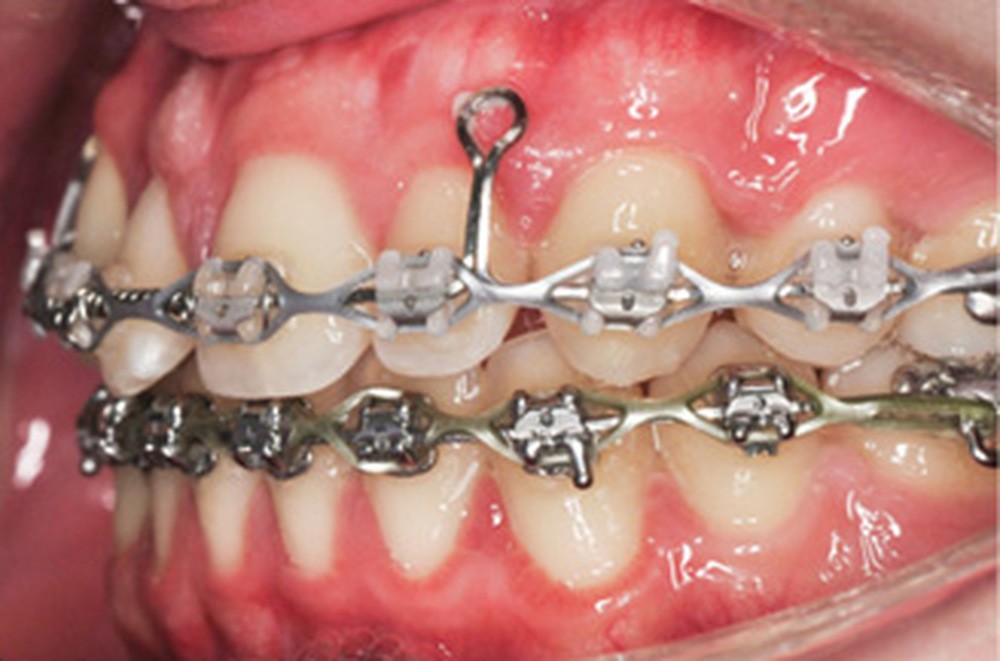

Le nivellement a nécessité trois arcs en Copper-NiTi (.014/.016 x .022/.019 x .025). Les mécaniques intra arcades (fermeture des espaces) et interarcades (élastiques de tractions intermaxillaires de classe II) ont été effectuées sur des arcs en acier .019 x .025. La gestion asymétrique de la mécanique de rétraction maxillaire a débuté par le recul de 23 (ancrage postérieur dentaire + élastiques intermaxillaires de classe II). Une fois 23 symétrisée avec 14 (substituant la 13), le centrage de 12 a débuté pour le remplacement de la 11. La rétraction du groupe antérieur par un arc à boucles de rétraction en acier .019 x .025 permet d’ajuster le torque radiculo-palatin pour contrer le rabbiting antérieur (fig. 2a-c).